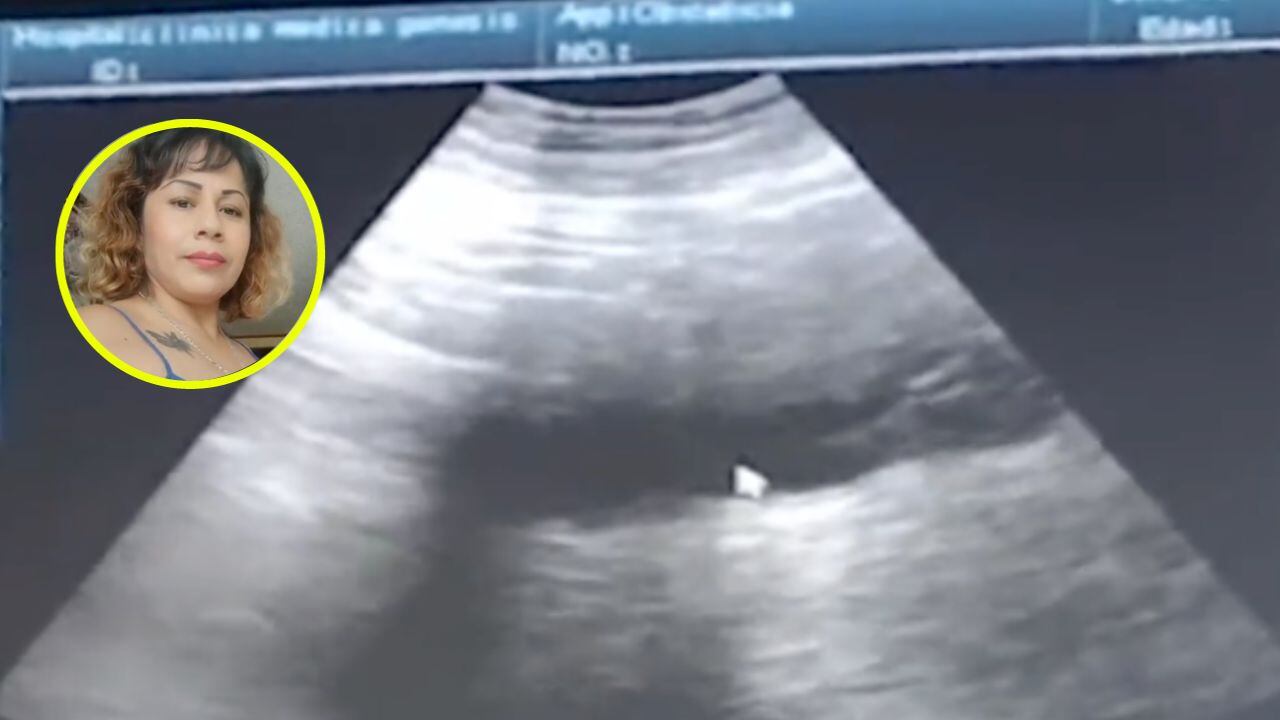

En las últimas horas, las redes sociales se inundaron de la denuncia realizada por una pareja contra una clínica por el supuesto robo de sus mellizos recién nacidos. El periodista Carlos Jiménez fue uno de los tantos comunicadores que utilizó su cuenta de Twitter para mostrar evidencia de las citas en las que le aseguraban a la mujer que estaba embarazada: “Hasta le dijeron cuánto pesaban sus mellizos. Así le hicieron estudios y ultrasonidos a Liliana. Planearon su parto. 9 meses después, tras someterla a cesárea, los mismos médicos le dijeron que se equivocaron y que eran 2 tumores”.

Mediante el medio NMás, Danielle pudo documentar las palabras de la madre de familia que, durante nueve meses, pesó que volvería a dar a luz: “Si, yo voy al doctor el día 27 de diciembre de 2022 porque tengo un dolor muy fuerte de ovarios y cadera; en un hospital que se llama Génesis, es una clínica que se llama clínica Génesis 21″, comenzó explicando la entrevistada.

La paciente aseveró que el primer diagnóstico fue “una fuerte infección de vías urinarias, pero que me iba a poner antibiótico muy leve porque estaba probablemente embarazada”. Liliana se alegró por la noticia. Como cualquier otro embarazo, la mujer acudió a estudios, ultrasonidos e incluso le dieron los latidos coronarios de los bebés.